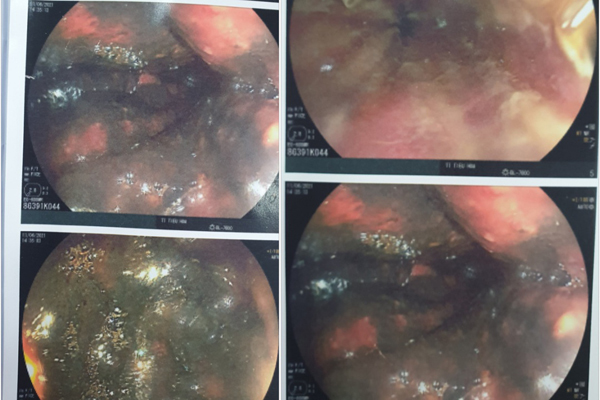

Kết quả nội soi toàn bộ đường tiêu hóa cho thấy, niêm mạc thực quản, niêm mạc dạ dày và niêm mạc hành tá tràng bị phù nề, xung huyết mạnh, dạ dày có nhiều dịch đen bẩn.